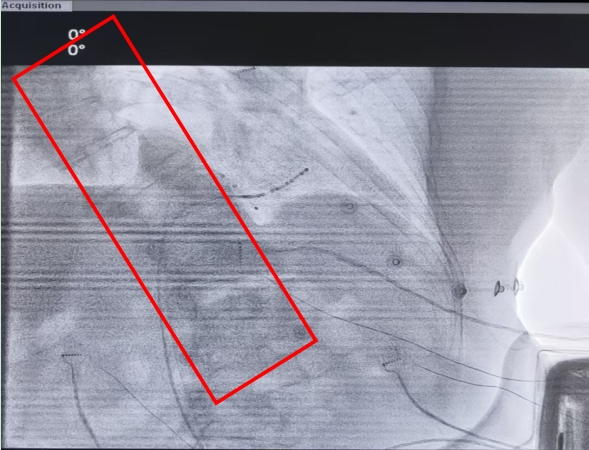

由于此次手术需经下腔静脉抵达心脏,但金先生不仅存在鸡胸合并驼背的情况,还伴有脊柱侧弯变形,致使心脏位置发生明显移位。这使得手术导管要通过下腔静脉进入心脏面临着超乎想象的困难。术中,导丝在通过畸形血管时,甚至都被挤压变形,情况一度十分棘手。

心内科团队迎难而上,反复查阅患者术前CT,结合术中心脏造影,借助可调弯鞘管和穿刺导丝成功穿刺房间隔,消融手术取得成功,金先生也安全顺利地返回了病房。